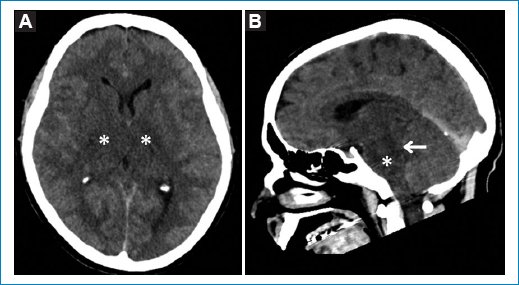

Respecto a los cinco pacientes con hallazgos patológicos agudos en la TCC, cuyas características demográficas y clínicas se describen en la tabla 2, se reconocieron un ACV isquémico agudo en el territorio de la arteria cerebral media derecha (Fig. 1), un edema cerebral difuso por encefalitis (Fig. 2), una encefalopatía necrotizante aguda (Fig. 3) y dos hematomas intracraneales intraaxiales, de los cuales uno en se ubicó en los núcleos de la base del hemisferio cerebral izquierdo y el otro en el lóbulo parietal derecho (Fig. 4). Todos ellos correspondieron a cuadros de dengue grave.

Figura 1. TCC de una paciente de 81 años con ACV isquémico agudo en el territorio de la arteria cerebral media derecha. Obsérvese el área hipodensa cortical y subcortical fronto-parieto-temporal con leve efecto de masa (asteriscos). Imágenes axial (A) y coronal (B).